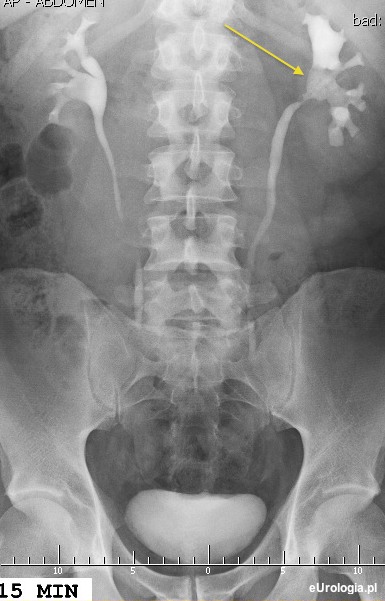

Guz miedniczki nerkowej jest w większości przypadków rakiem urotelialnym czyli rakiem wywodzącym się z nabłonka wyścielającego drogi moczowe. Guzy miedniczki nerkowej najczęściej diagnozowane są na podstawie urografii lub tomografii komputerowej z kontrastem. W urografii charakterystycznym objawem jest ubytek wypełnienia - zakontrastowania miedniczki nerkowej. Leczenie endoskopowe może być diagnostyczne lub terapeutyczne. Najczęściej wykonuje się ureterorenoskopię czyli wziernikowanie moczowodu i miedniczki nerkowej, w czasie którego pobierane są wycinki do badania histopatologicznego.

Fot. Urografia wykonana u pacjenta z guzem miedniczki nerki lewej - widoczny ubytek zakontrastowania UKM.